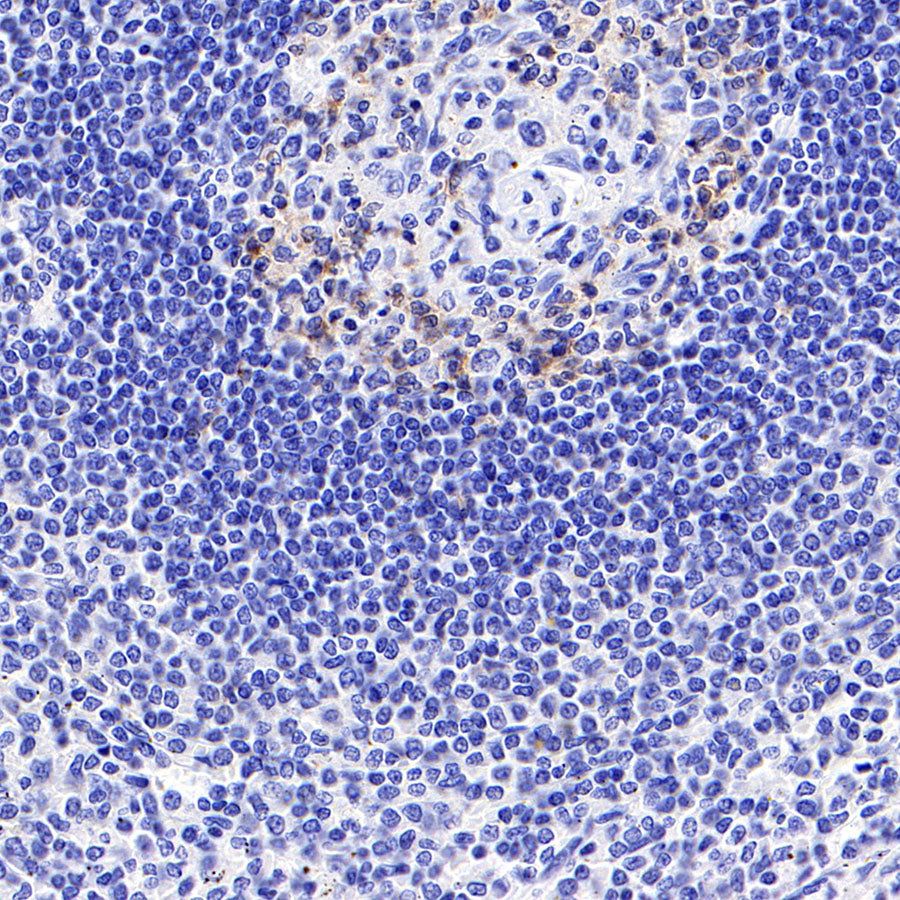

Immunohistochemistry

IHC shows positive staining in paraffin-embedded human spleen. Anti-PD-1 antibody was used at 1/500 dilution, followed by a HRP Polymer for Mouse & Rabbit IgG (ready to use). Counterstained with hematoxylin. Heat mediated antigen retrieval with Tris/EDTA buffer pH9.0 was performed before commencing with IHC staining protocol.

Negative control: IHC shows negative staining in paraffin-embedded human liver. Anti-PD-1 antibody was used at 1/500 dilution, followed by a HRP Polymer for Mouse & Rabbit IgG (ready to use). Counterstained with hematoxylin. Heat mediated antigen retrieval with Tris/EDTA buffer pH9.0 was performed before commencing with IHC staining protocol.